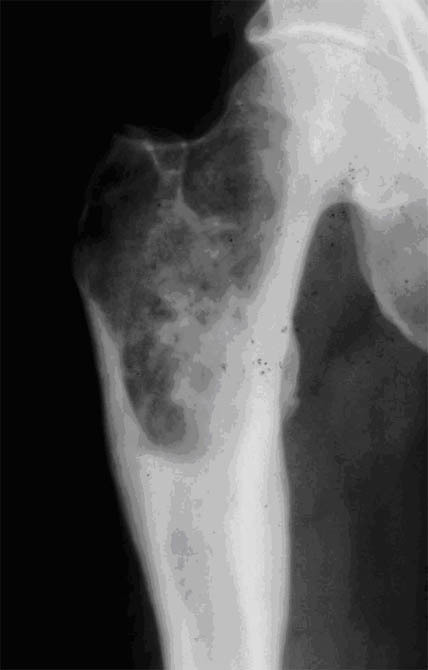

Q

Quel est le stade Garden de cette fracture de l’ES du fémur? Quel est le risque évolutif principal?

A

Fracture ES fémur garden 4 car perte de contact entre fragments,

les travées osseuses sont normales

Risque max d’ostéonécrose aseptique